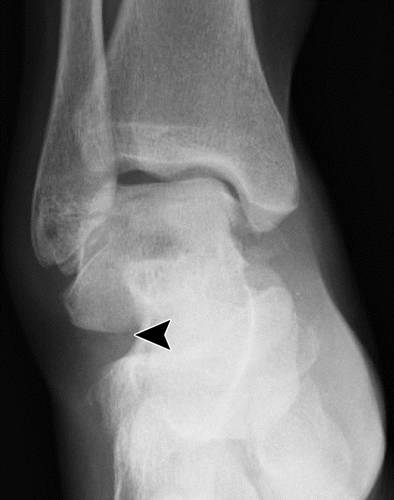

这种损伤必须与三角骨 - 一个附件后骨小梁区分开来。 在放射照相术中,后过程的断裂显示不规则的边缘(图13),而三角骨是圆形或椭圆形,具有光滑的皮质边缘(图14)。 双侧X线照片的价值有限,因为据报道三分之二的病例是双侧的(32)。 如果射线照片不确定,应进行CT。

图13b后突骨折。 (a)右足的外侧X光片显示在距骨后方的小骨质碎片(箭头)。 (b)右脚的轴向CT图像显示后路过程骨折(箭头)以及粉碎的程度和程度。